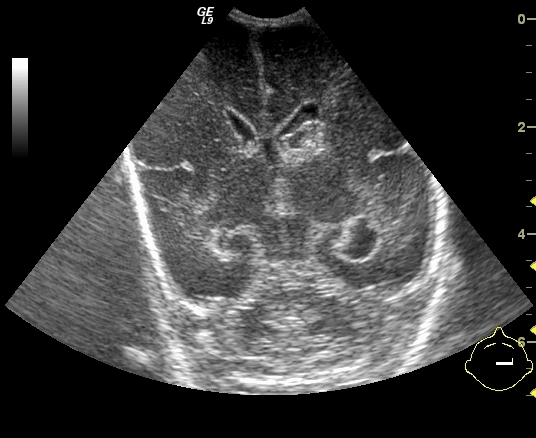

Distal urethral valve (subvesical obstruction). It is the most severe form of obstructive uropathy. In newborn boys the valve dysfunction can lead to bilateral obstruction with hydronephrosis and hydroureter. Urination can only occur intermittently. The bladder wall is thickened, trabecular and reflux is frequent. The proximal urethra is distended as well.

23. Miction cystourethrography. A small diverticula is seen on the right side, the proximal urethra is dilated, beneath is a filling defect. Subvesical obstruction, dorsal urethral valve.